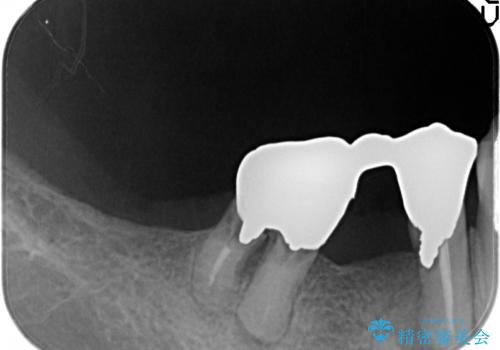

右の上下の歯を抜歯してインプラントを埋入して、かぶせ物を装着する計画としました。

右側のかみ合わせを回復するには、インプラントか入れ歯のどちらかの方法で治療する必要があました。

治療方法について十分な説明を行い、インプラント治療を選択されました。